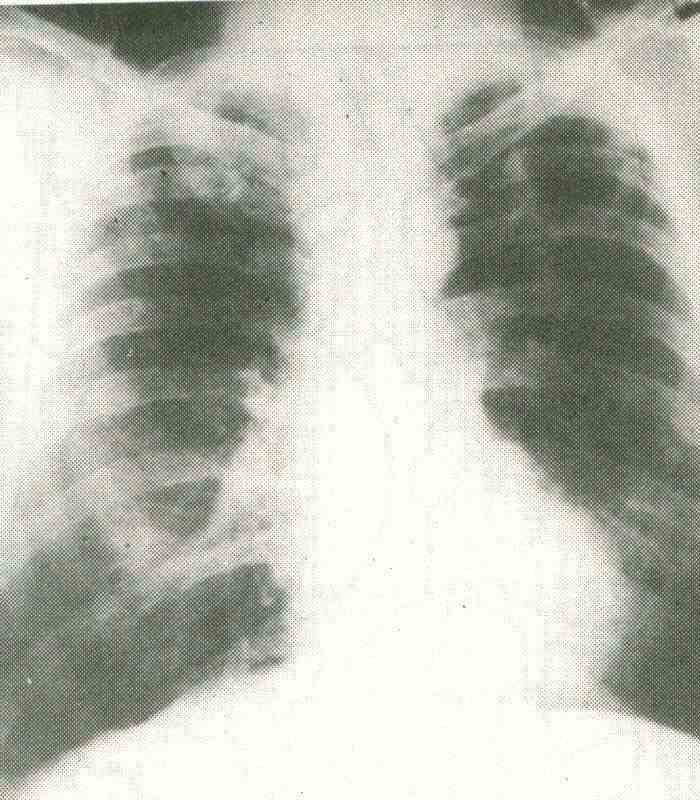

La caverna tuberculosa puede ser unica o múltiple, pequeña o grande, y se localiza mas frecuentemente en el segmento apical del lóbulo inferior y en los segmentos apical y posterior del lóbulo superior (fig 16-

3). Puede tener nivel hidroaereo con una pared que mide de 2 a 5 mm de espesor y contornos lisos o irregulares.